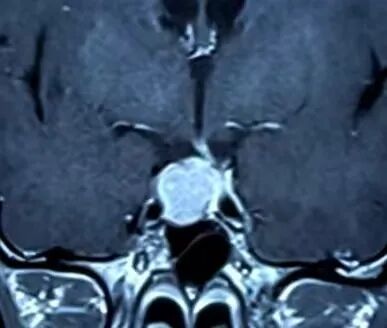

患者垂体瘤核磁共振影像

“那段时间整个人都很煎熬,头痛反复发作,月经也不规律。”张女士回忆道。多家医院初步诊断为“鞍区占位性病变”,但治疗方向未明。直至来到市二院神经外科,桑文渊主任与北京三博脑科医院张宏伟教授通过远程会诊,结合影像学和内分泌检查,确诊患者为垂体大腺瘤。考虑到肿瘤体积较大,且已引发明显临床症状,团队一致认为手术切除是最佳治疗方案。

经过周密准备,手术如期进行。张宏伟教授与桑文渊主任团队密切配合,采用经鼻蝶入路微创手术,在显微镜下完全切除肿瘤,同时完美保护了视神经和颈内动脉等重要结构。术后病理证实为垂体瘤伴卒中,与患者术前症状完全吻合。